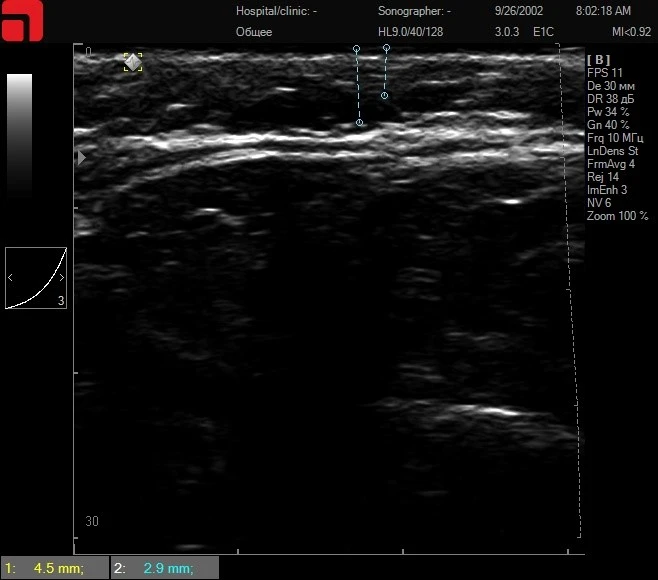

Ключевым фактором в определении оптимального пациента является проведение ультразвуковой диагностики кожи высокого разрешения, так как она позволяет выделить пациентов с большим содержанием соединительной ткани в подкожно-жировой клетчатке и на СМАС-слое (здесь и далее все ультразвуковые сканограммы сделаны на аппарате Doublo).

Рис. 1. На снимке отмечается большое количество соединительнотканных септ и трабекул в подкожно-жировой клетчатке, а также выражена фасция, покрывающая СМАС-слой.

Так как мишенями для проведения HIFU SMAS-лифтинга является именно соединительная ткань в подкожно-жировой клетчатке и на SMAS, их высокое содержание обеспечивает яркую выраженность результатов (рис. 1). При проведении HIFU SMAS-лифтинга создаются точки коагуляции в области соединительной ткани, что приводит к сокращению ее площади, укреплению и запуску процессов лифтинга. Проводя ультразвуковую диагностику кожи высокого разрешения, специалист всегда выявляет пациентов с большим количеством соединительной ткани и может с уверенностью назначать им монопроцедуру без подключения дополнительных методов в курсе лечения.